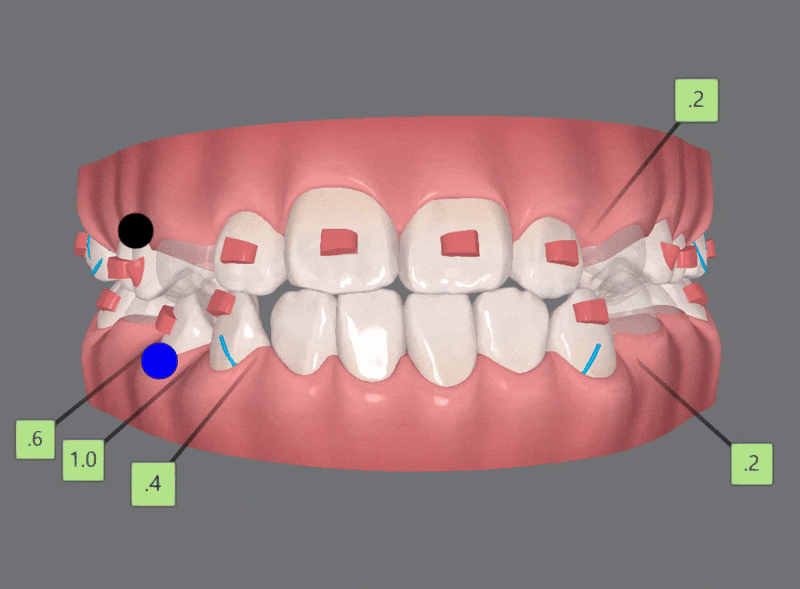

1st ClinCheck(30개)

첫번째 클린체크의 영상입니다.

인비절라인의 장점 중의 하나는

교정 후의 모습을 예측할 수 있는것 입니다.

원장님께서 클린체크 디자인을 마치게 되면

인비절라인 교정치료 후에

치아이동이 어떻게 변화하는지 클린체크를 통해 확인 해 볼 수 있는것인데요.

첫번째 클린체크에서는 총 30개의 장치로

진행 해드렸습니다.

인비절라인 첫번째 클린체크 30개의 장치로

치아끼리 맞닿고 있던 앞니들이

개선되면서

윗니가 아랫니를 덮는 정상에 가까운 교합 상태로 개선되었습니다.